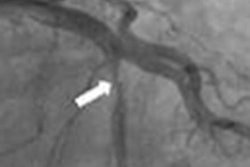

Axial contrast-enhanced CT images from (a) a 13-year-old, 58.3-kg male patient and (b) a 4-year-old, 13-kg male patient were reconstructed at 3-mm and 0.5-mm image thicknesses with filtered back projection (FBP), statistical-based iterative reconstruction (SBIR), model-based iterative reconstruction (MBIR), and deep-learning reconstruction (DLR). Images and caption courtesy of Radiology.After a mathematical observer model was used to perform an objective comparison of the images produced by the various reconstruction methods, three fellowship-trained pediatric radiologists then provided a subjective comparison of the images. These observers assessed anatomic structures with low object-to-background signal and contrast to noise in the azygos vein, right hepatic vein, common bile duct, and superior mesenteric artery, providing ratings ranging from 1 (worst) to 10 (best) for edge definition, quantum noise level, and object conspicuity.